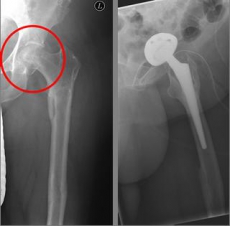

In addition to a thorough physical examination, radiographs of the pelvis and the affected hip are crucial for the diagnosis.

Oberschenkel 1          Oberschenkel 2

Images: Here is the supply of a dynamic hip screw shown.

In younger patients and a minor shift, the goal is to preserve the femoral head. The blood supply to the femoral head is at risk for medial femoral neck fractures, so that the fastest possible care should be sought if one wants to preserve the femoral head. Among others, the dynamic hip screw (DHS) is available for this purpose.